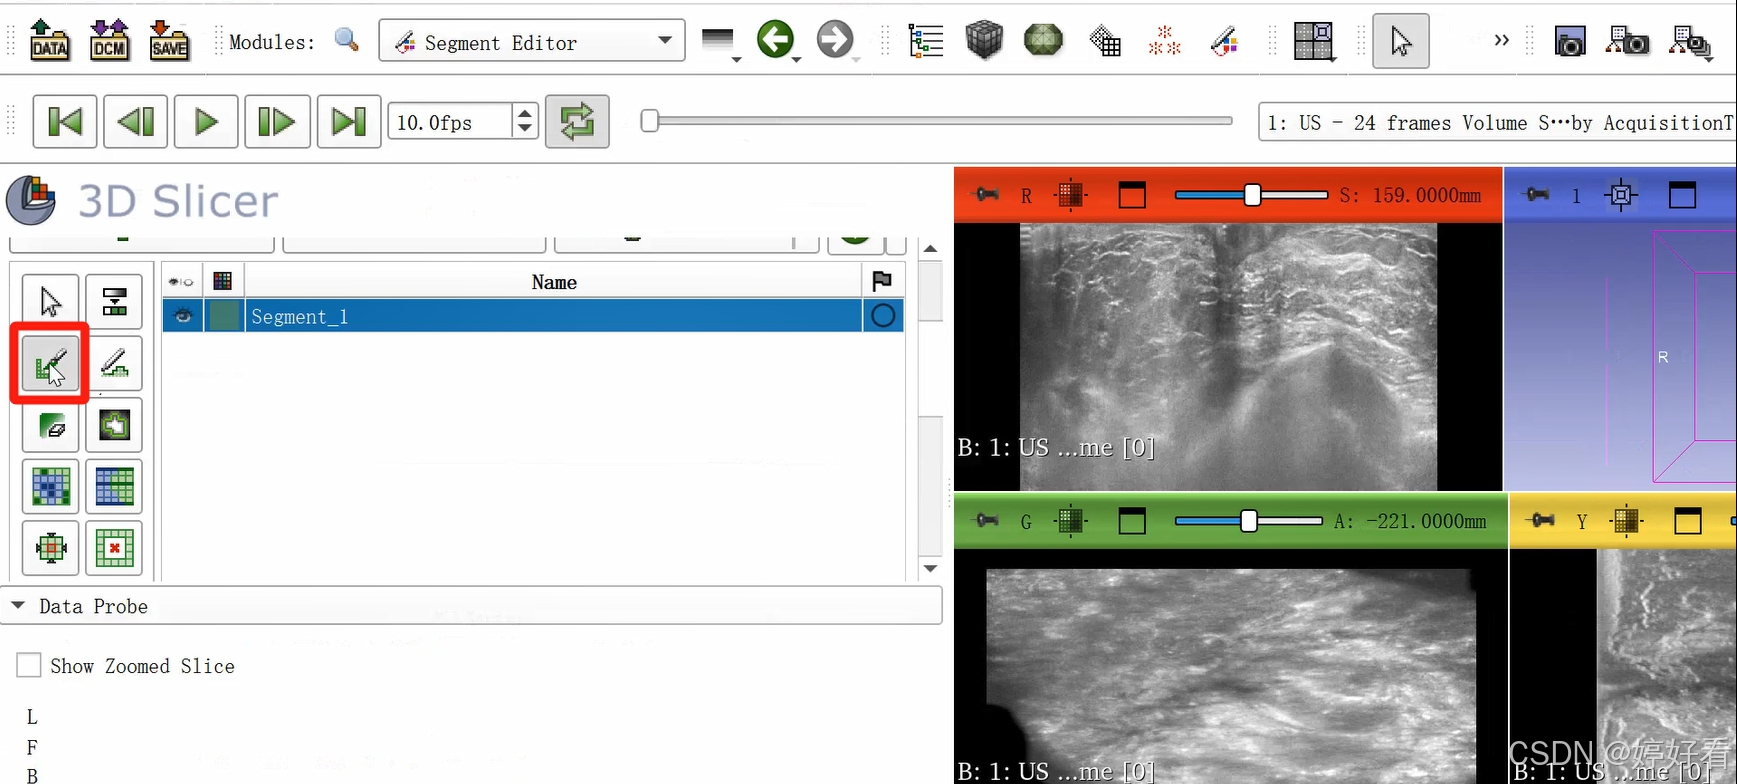

2.3 使用Paint功能勾画感兴趣区域。

可以隔两三层画一次(示例中为随意勾画,大家在实际操作中可以请专业的医生确认感兴趣区域)。

这是一个三维的图像,我们只要在一个面上勾画就可以了,另外两个面会自动显示勾画的区域。